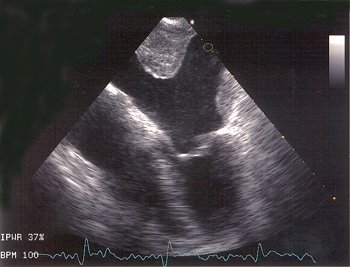

Die transösophageale Echokardiographie (TEE)

Spezielle Ultraschalltechnik zur Herzuntersuchung von der Speiseröhre aus.

Sonde (rechts im Bild) in der Speiseröhre direkt hinter dem Herzen

Thrombus (Gerinnsel) im linken Herzvorhof